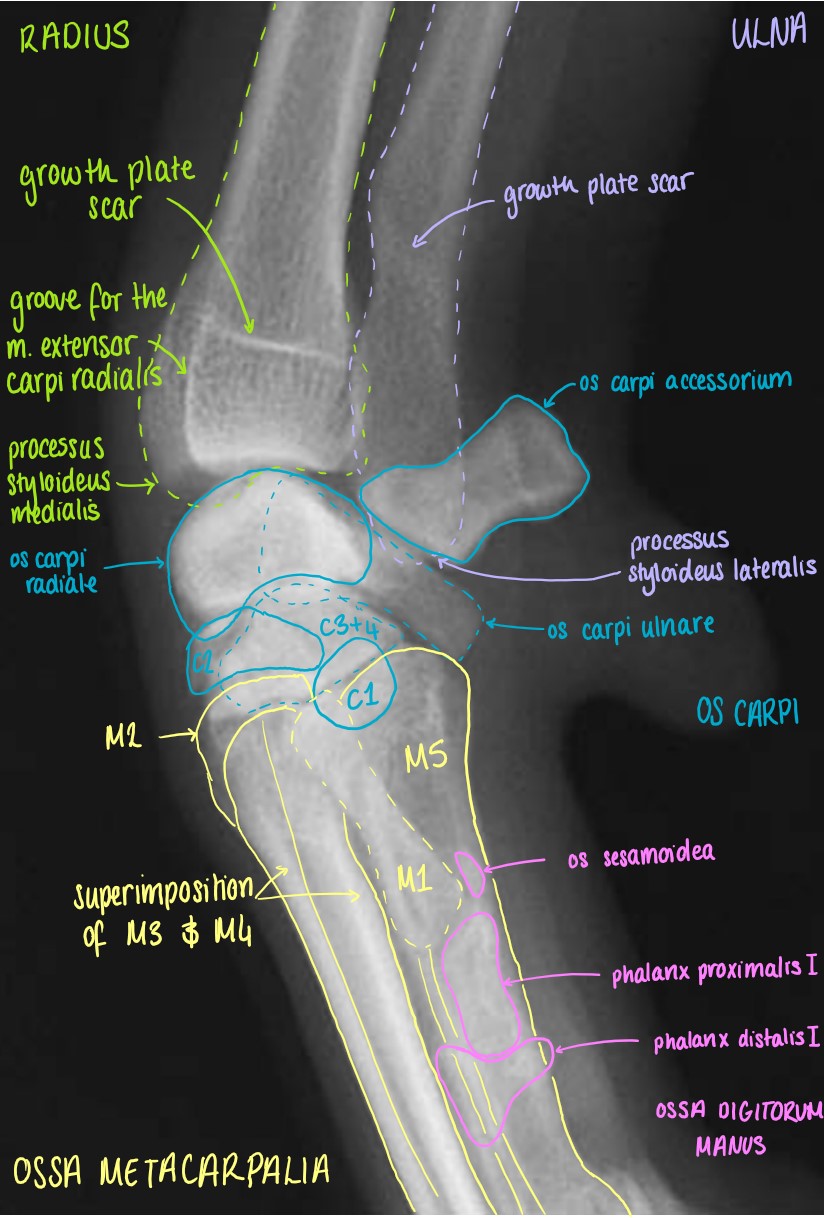

Articulatio Carpi

Manus